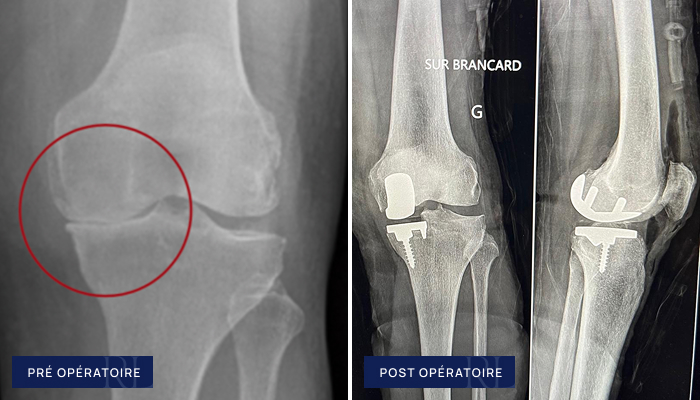

Avant / après Gonarthrose

Gonarthrose (Prothèse totale de genou sur mesure – PTG)

À gauche : Usure globale du cartilage du genou (gonarthrose tricompartimentale)

À droite : Prothèse totale du genou, sur mesure